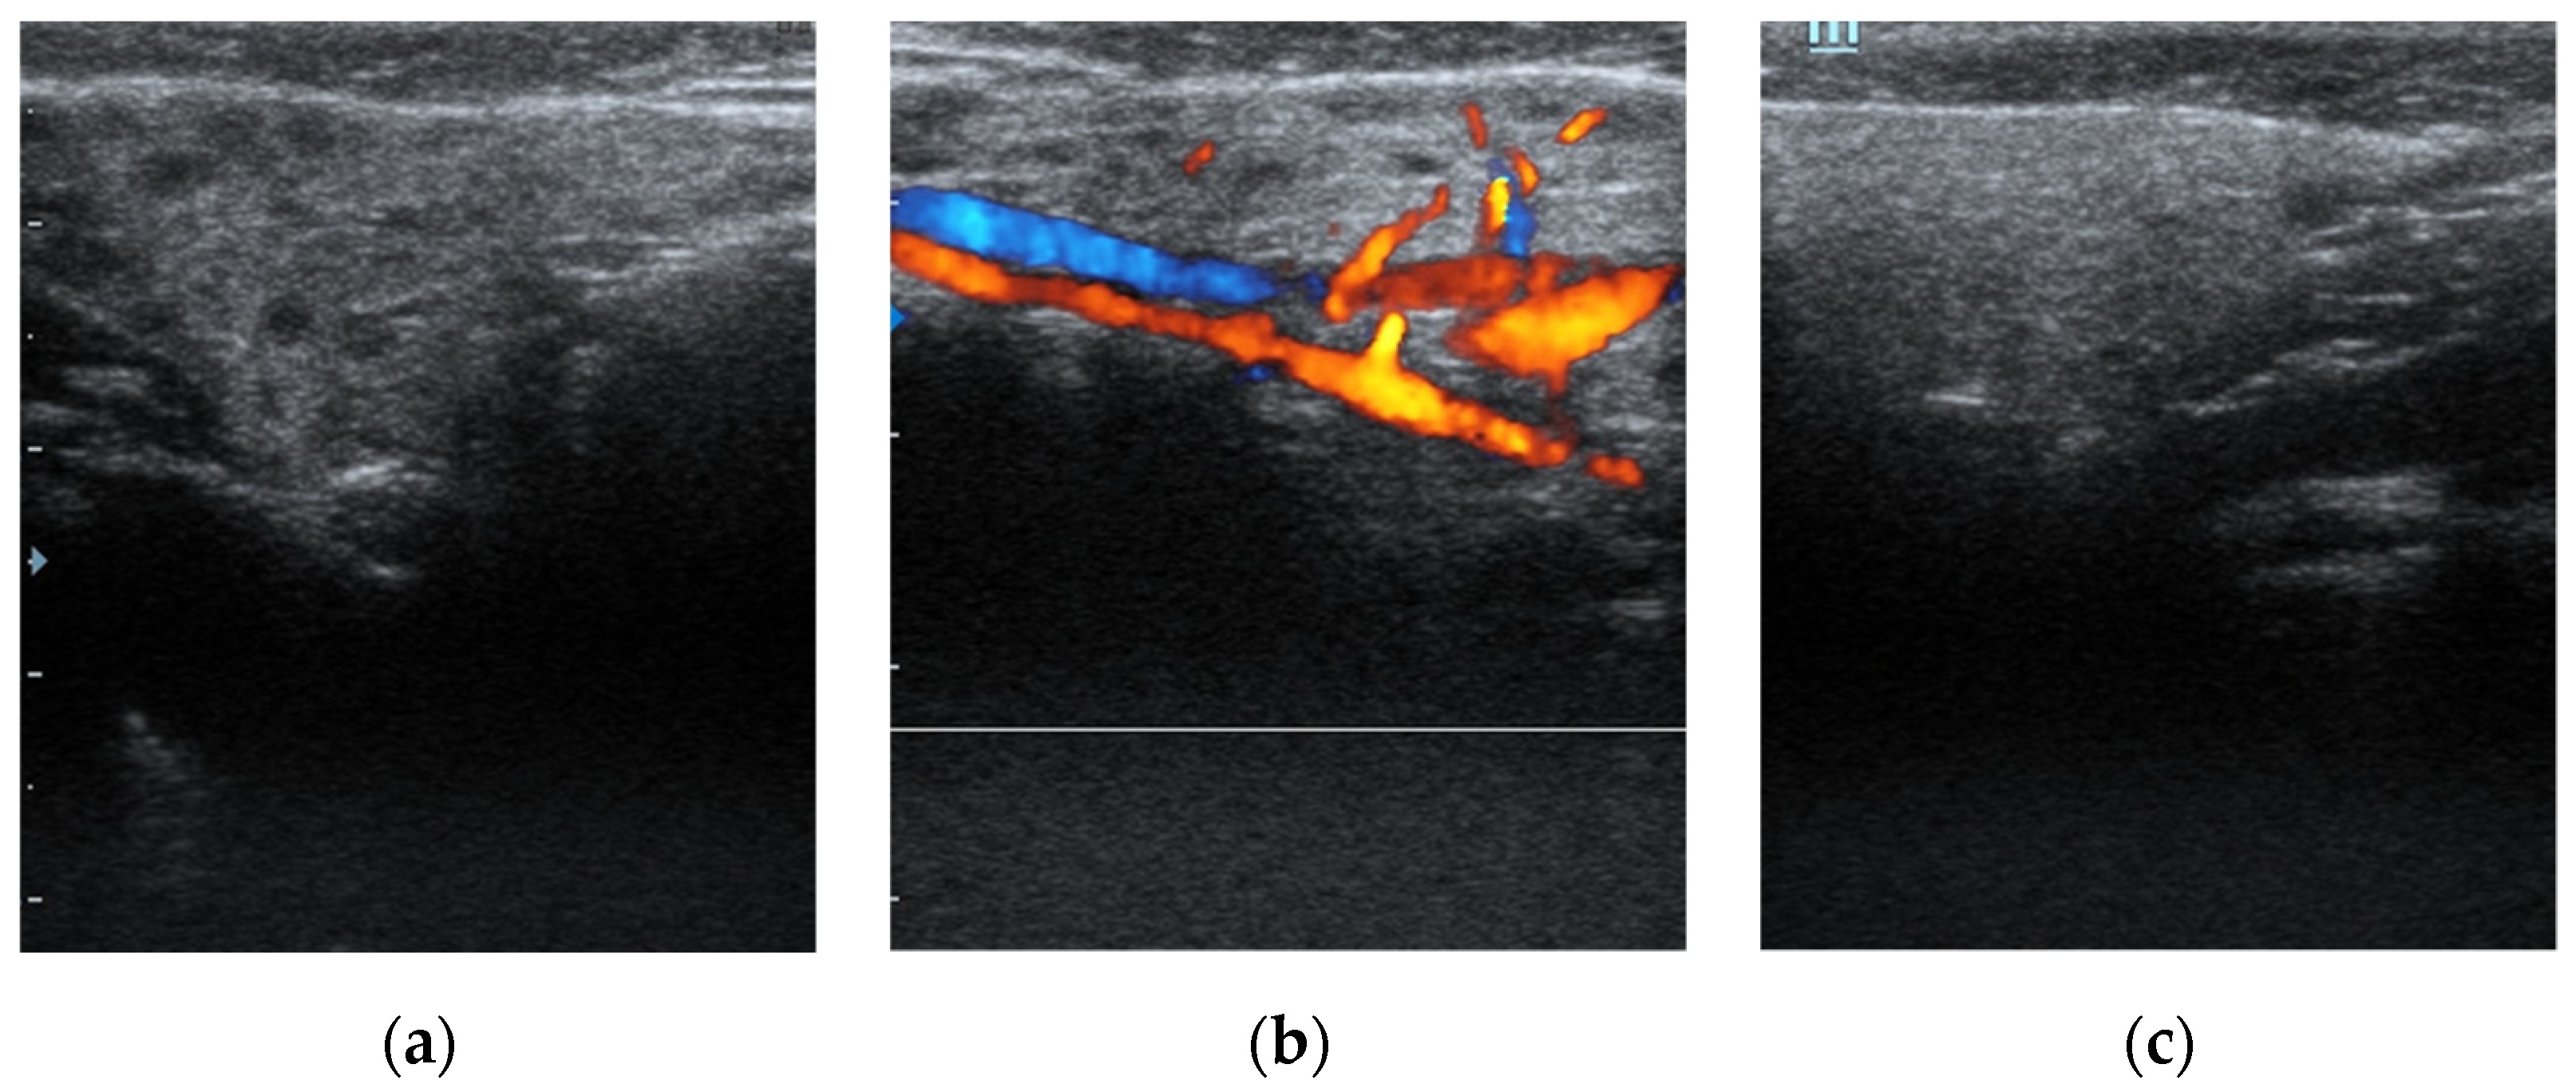

During the procedure, the main duct was examined—there was a pale appearance of ductal wall, individual capillaries, and mucous plugs noted to various extent within all patients (Figure 2). Eight patients (38%) had stenosis present and seven had stenosis with a grade of S2 or higher. The mean depth of endoscope introduction into the duct system was 59.1 ± 13.6 mm (range, 22–87 mm). During two procedures, the ductal wall was damaged, therefore we stopped the intervention. In both, steroids were instilled into the duct before this event, and later restitutio ad integrum state was re-established. Consequently, the intraoperative complication rate was noted within 7% of procedures, however, there were no late complications observed or reported.

Figure 2. Sialendoscopic appearance of the parotid duct. (a) displays the endoscopic appearance of pale mucosa. (b) depicts guiding wire introduced during the sialendoscopic procedure to overpass the stenosis. (c) shows mucus in the main salivary duct.